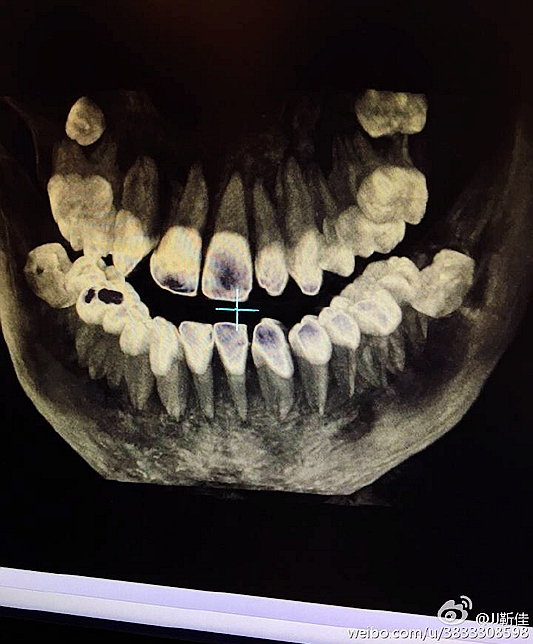

2016.8.3涉縣美康口腔王主任種植牙于額外牙拔除

左下67缺失

今年的額外牙真多啊 男孩14周。

ct定位

術(shù)后拍片